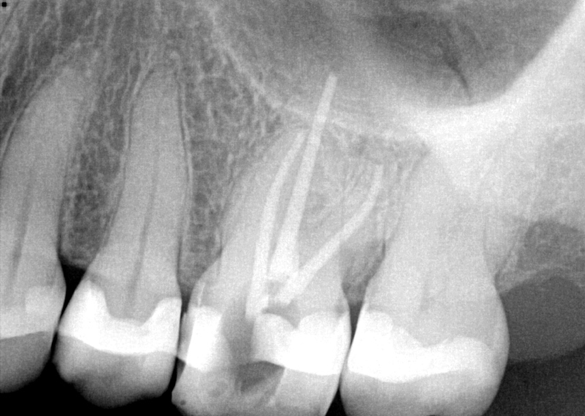

Fig 7. Primary endodontic and secondary periodontal lesion, mandibular second molar.

Figure 7

In Figure 7, the periapical radiograph identifies the presence of the combined endodontic-periodontal lesion developing due to a carious lesion beneath an existing vintage gold crown with ill-fitting margins. Intraoral examination revealed a fistula developing and moderate pain on percussion and mastication. After occlusal access and clear visualization of the canals, the canals were shaped using the rotary files, with precautions taken not to perforate or enlarge the apical foramen. Maintaining the endodontic therapy within the canals prevents the infection from being introduced into the surrounding periodontium. In this case, calcium hydroxide medicament was placed into the canals and evaluated 30 days postoperatively.8